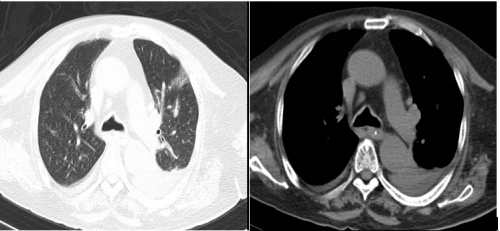

10月14日胸部CT检查:

10月15日